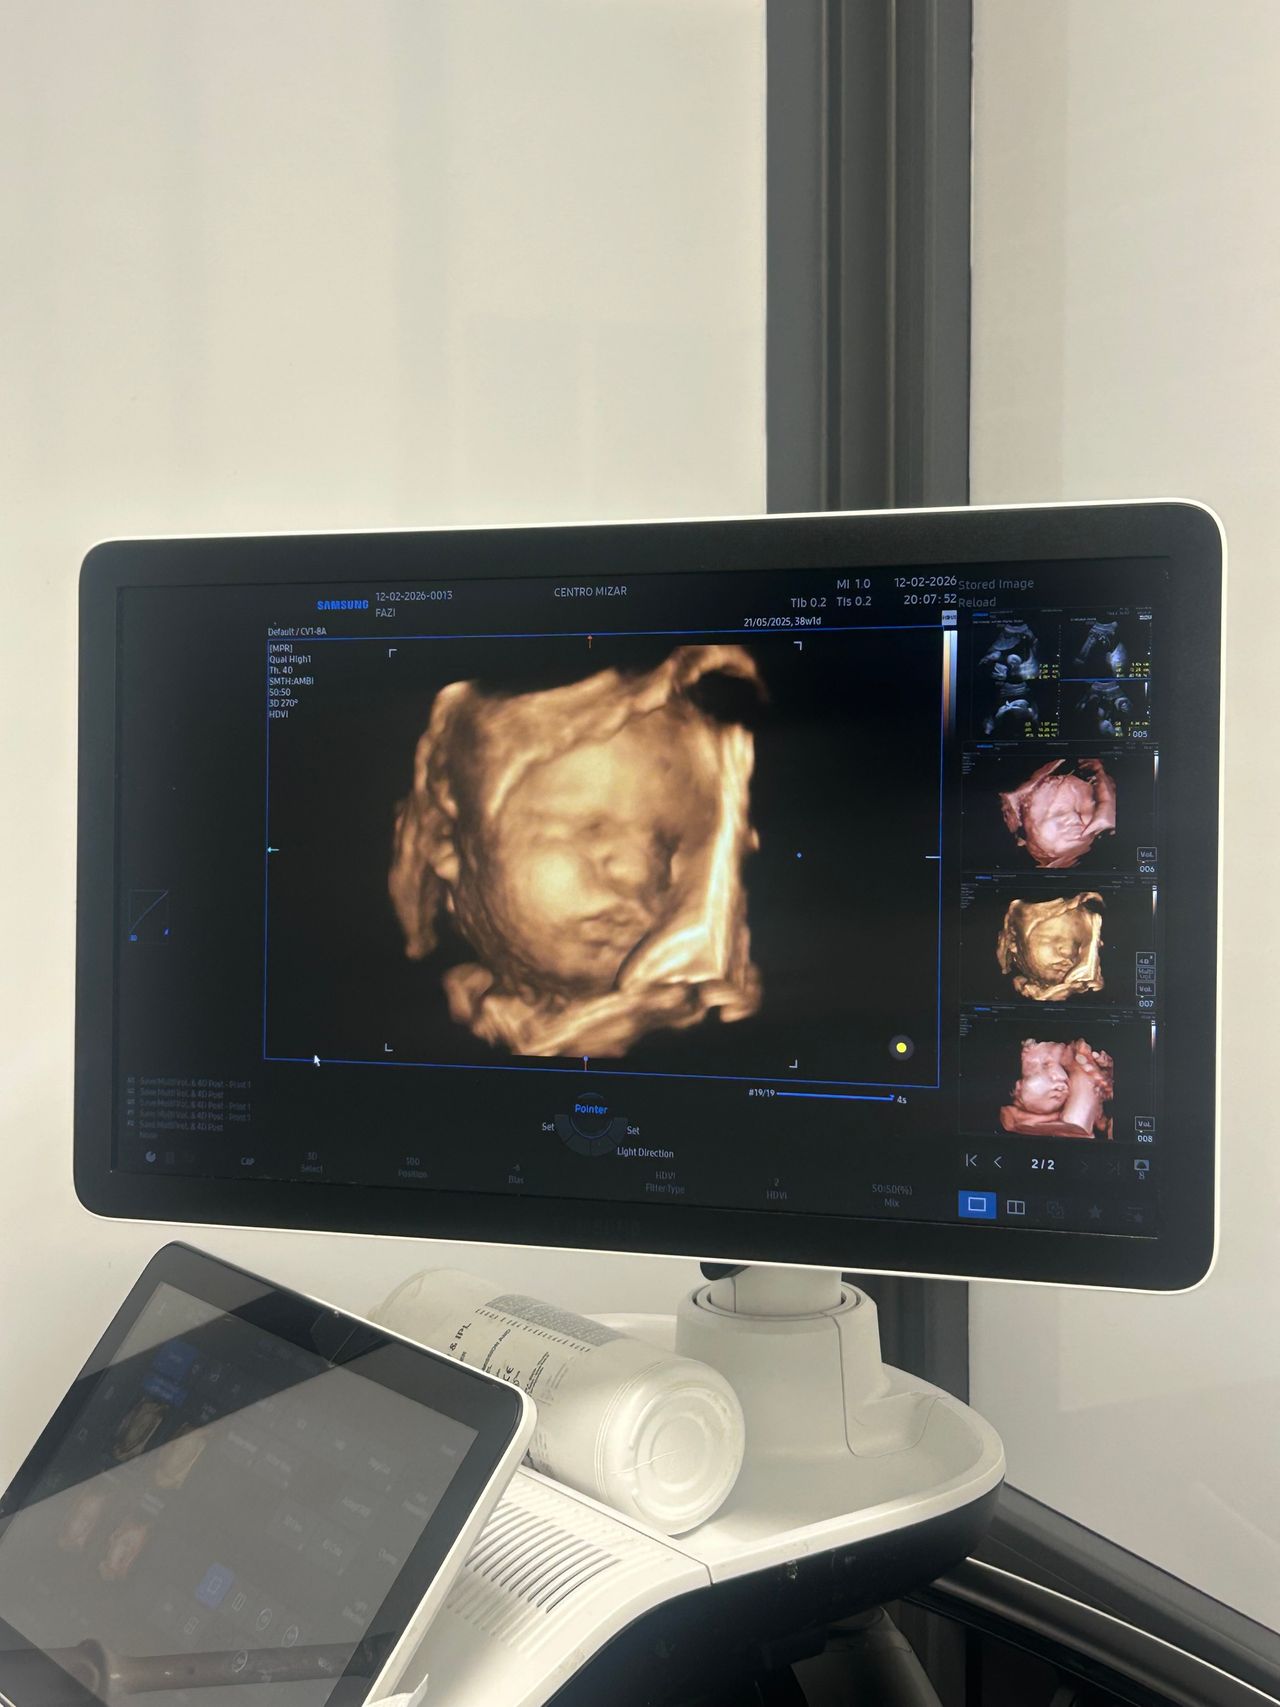

Laureata con Lode e Menzione alla carriera presso l’Università degli studi di Firenze e Specializzata con Lode presso L’ Università Cattolica del Sacro Cuore (Fondazione Policlinico A. Gemelli) mi occupo principalmente di Diagnostica Ecografica Ginecologica ed Ostetrica. Certificata dalla Fetal Medicine Foundation con sede a Londra per l’esecuzione dei Bitest, svolgo ecografie ostetriche per tutti i trimestri di gravidanza (premorfologiche, morfologiche, ecografia del III trimestre con flussimetria fetale).

Foto e video

Mizar medicina specialistica